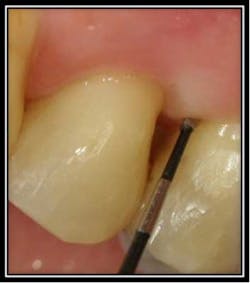

By Dr. Robert Gottlieb and Suzanne Newkirk, RDH The below pictures and corresponding video show an enamel pearl found on a molar tooth that developed a periodontal infection with a 6mm pocket depth. With Perioscopy, the doctor removed the enamel pearl quickly and efficiently with no post treatment discomfort or downtime for the patient.

Enamel pearl MB #3 pre treatment